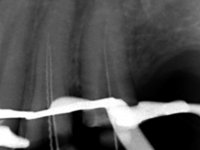

Paciente do sexo masculino, com 42 anos de idade, não fumador. Apresentava uma reabilitação metalo -cerâmica feita há mais de 10 anos com exposições radiculares e infiltrações. No maxilar superior apresentava uma coroa no 1.1,uma ponte de dois elementos no 2.1 e 2.2.e uma ponte de 4 elementos nos dentes 2.4,2.5,2.6 e 2.7 com o 2.6 como pôntico. Os dentes 1.6/1.5/1.4/1.3/1.2/1.1/2.1/2.2/2.3/2.4/2.5 e 2.7 apresentam tratamento endodôntico radical com o 2.4/2.5 e 2.7 a necessitarem de ser refeitos. No maxilar inferior apresentava uma ponte metalo-cerâmica de 4 elementos nos 4 incisivos e uma ponte de 3 elementos (3.3 e 3.4) com um dente supranumerário como pôntico. Os dentes 4.6/4.5 e 4.2 apresentavam tratamento endodôntico com o 4.2 a necessitar de ser refeito. Os dentes 4.3 e 4.4 apresentavam extensas cáries linguais com algum comprometimento mesial. As peças protéticas apresentavam-se infiltradas com exposição radicular associada. Apresentava uma D.V.O. diminuída e uma mordida cruzada lado direito. O paciente tinha uma satisfatória saúde periodontal e uma boa higiene oral.

A primeira acção terapêutica foi tentar melhorar o tratamento endodôntico dos dentes (2.4/2.5/4.2)). A sua manutenção em boca seria condicionada pelo sucesso desta intervenção. Seguidamente foram feitas impressões em alginato e registo inter-maxilar em silicone para confeção em laboratório de uma ponte provisória em acrílico com reforço. O objetivo desta ponte provisória seria ensaiar o aumento da D.V.O. e descruzar a mordida do lado direito. Foi utilizado um monobloco de 13 dentes com o dente 2.6 com o pôntico. As coroas e as pontes foram removidas e os remanescentes coronários foram repreparados. A ponte provisória foi rebasada primeiramente com acrílico auto-polimerizável e de seguida com resina composta. Após 2 semanas de permanência em boca, foram feitas as impressões para confeção da ponte provisória inferior também realizada em laboratório. Especial cuidado foi colocado na remoção das coroas antigas, sendo feito primeiramente um corte axial que permitiu que fossem removidas de uma forma menos traumática. A temporização foi feita durante 8 semanas, permitindo que os tecidos gengivais estabilizassem posicionalmente. As impressões definitivas foram realizadas após afastamento gengival utilizando a técnica do fio único impregnado. Foi utilizada a técnica de dupla mistura com dupla viscosidade (putty soft e light).Simultaneamente foi realizada a recolha das relações inter-maxilares e o registo com arco facial. Foram confecçionados os modelos de trabalho e feita a sua correta montagem em articulador semi-ajustável. Em seguida foram feitas infra estruturas em zircónia que posteriormente foram revestidas por cerâmica. A prova de “biscoito” foi realizada em boca para avaliação estética e funcional sendo também avaliado o seu assentamento e ajuste. A reabilitação definitiva foi cimentada em boca utilizando um cimento de ionómero de vidro reforçado por resina.